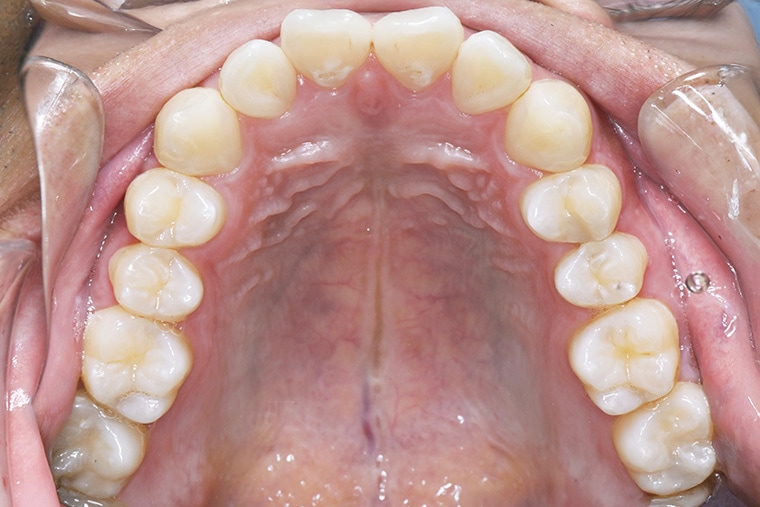

Case Study26歳男性出っ歯のマウスピース矯正-矯正期間8ヶ月(2023年11月開始)